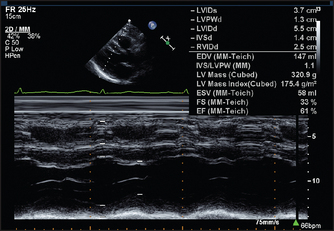

• In M mode, detailed information is provided from a single line of ultrasound. It is used to study motion in detail and to make measurements of chamber sizes (see Figures 8.12, 8.13 and 8.14).

Figure 8.12 Normal long-axis M mode measurements Both the fractional shortening (change in the dimensions between systole and diastole; normally >27%) and the ejection fraction have been calculated. (From Baker T, Nikoli

G, O’Connor S, Practical cardiology, 2nd edn. © 2008, Sydney: Elsevier Australia.)

Figure 8.13 M mode echo from a 34-year-old man with two months of increasing dyspnoea, diagnosed initially as asthma. The left ventricle is very dilated. The end-diastolic dimension is 70 mm (<57). The fractional shortening is only 14% (>25–27). Contraction of the septum and posterior wall are equally reduced, typical of dilated cardiomyopathy (page 110). (From Baker T, Nikoli

Figure 8.14 M-mode measurements in a patient with hypertension. There is symmetrical thickening of the left ventricular wall. (From Baker T, Nikoli

1. Structural and functional measurements. Assessment of left ventricular function by echo involves measurement of the left ventricular end-diastolic dimension (normally less than about 57 mm) and the end-systolic dimension. Figure 8.12 shows echo views of the heart in the long axis. It shows some of the measurements and structures that can be assessed in this standard view.